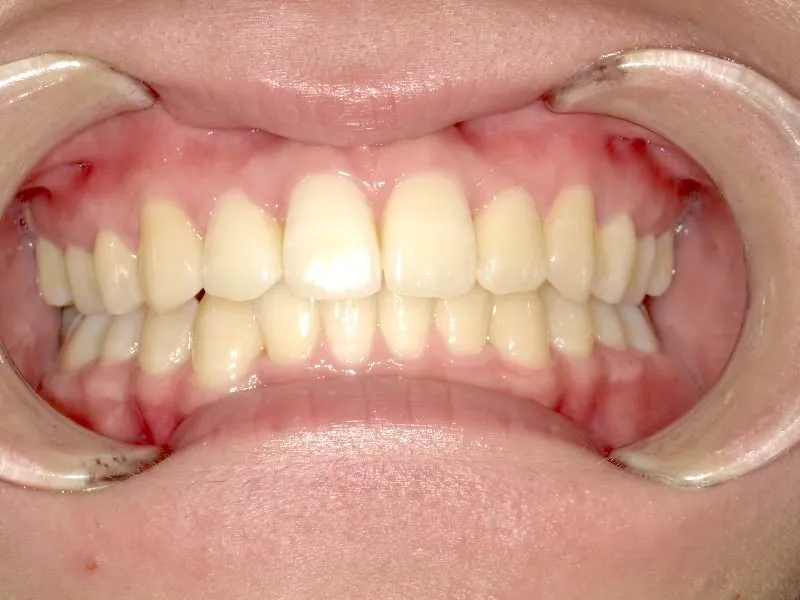

奥歯が内側と前方にかたむき上下の歯がガタガタに生えています。

90度ねじれた歯もあります。前歯も出っ歯になっています。

歯は抜かず、歯科矯正用アンカースクリューを用いて治療しました。

治療回数○回、2年9ヶ月の治療期間で矯正治療を終了しました。

主訴が改善され、ご満足頂きました。